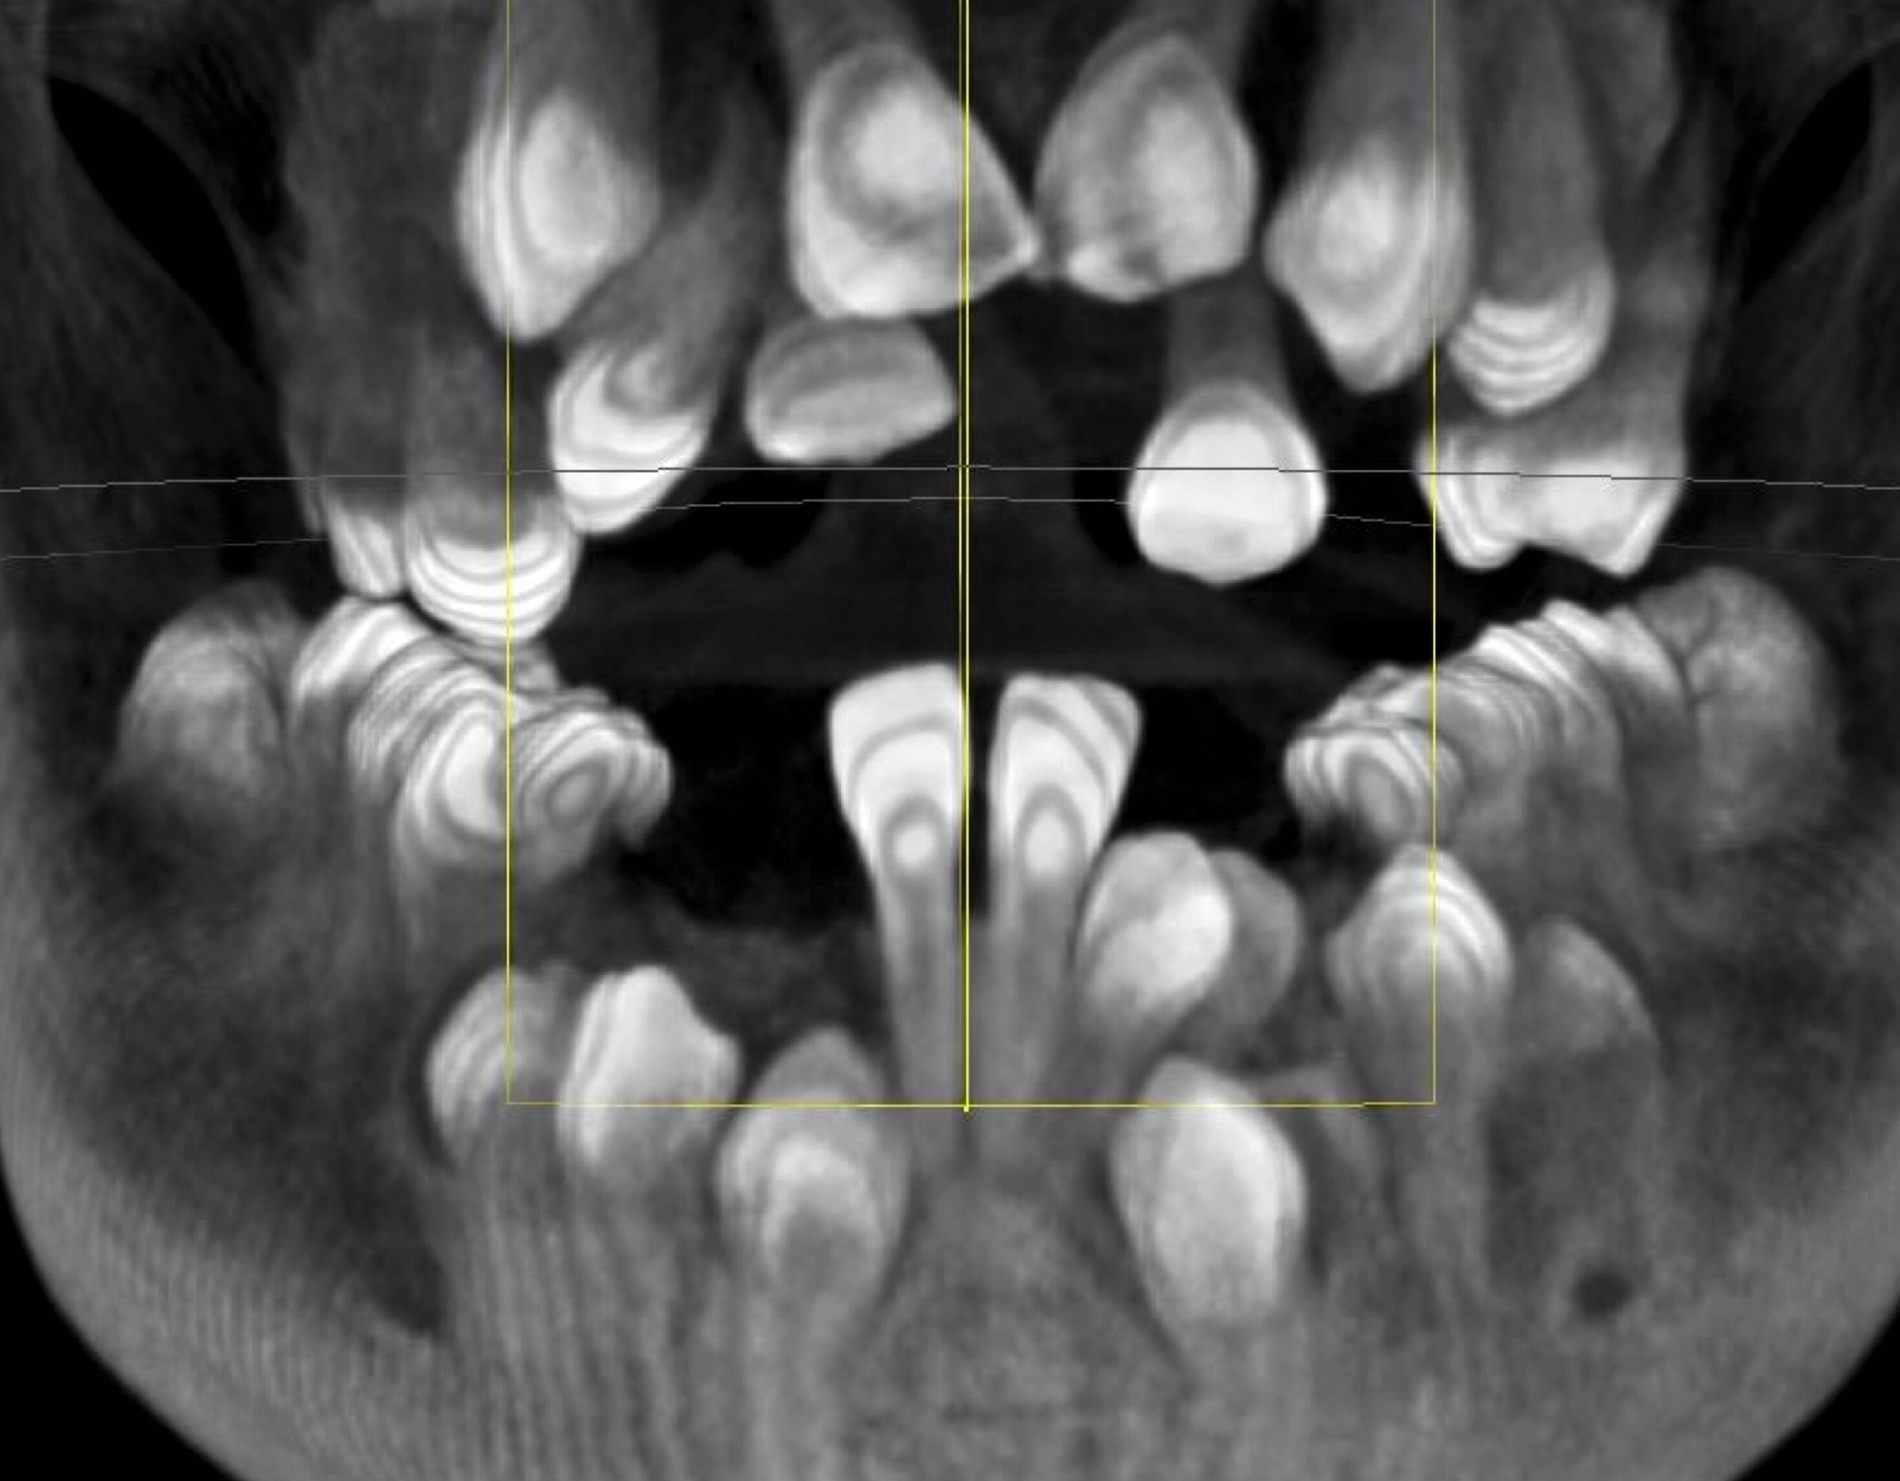

In Absprache mit dem/der zahnärztlich beziehungsweise chirurgisch tätigen Kollegen/in kann die Kieferorthopädie durch Umsetzung verschiedenster 3-D-gedruckter Elemente eine Hilfe in interdisziplinären Behandlungen bieten. Am Beispiel der Zahntransplantation ermöglicht der 3-D-Druck zuvor im DVT segmentierter Zähne eine passgenaue Vorbereitung des Transplantationsbettes (Abbildung 6a). 3-D-gedruckte Zähne können darüber hinaus als Lückenhalter während der kieferorthopädischen Behandlung dienen (Abbildung 6b), bevor eine definitive Versorgung durch den/die zahnärztliche/n Kollegen/in erfolgt.

Weitere Beispiele beinhalten hochkomplexe Behandlungsfälle multipler Zahnanlagen. Während die Extraktionsentscheidung und Absprache mit dem/der chirurgisch tätigen Kollegen/in allein auf Basis der Bildgebung oft limitiert ist, erleichtern 3-D-gedruckte Modelle des segmentierten DVTs sowohl die Entscheidung als auch die Absprache und ermöglichen darüber hinaus eine genauere Planung des chirurgischen Vorgehens (Abbildung 6c). Gleiches betrifft parodontalchirurgische Eingriffe, in denen sogenannte „Cutting guides“ eine zuvor digital geplante Gingivektomie ermöglichen (Abbildung 6d). Im Bereich der Freilegung verlagerter Zähne können Schablonen dem/die chirurgisch tätigen Kollegen/in sowohl die Freilegung des Zahnes (Abbildung 6e) als auch die Anbringung eines Attachments (Abbildung 6f) erleichtern und dabei die kieferorthopädisch gewünschte Attachmentposition passgenau übertragen.